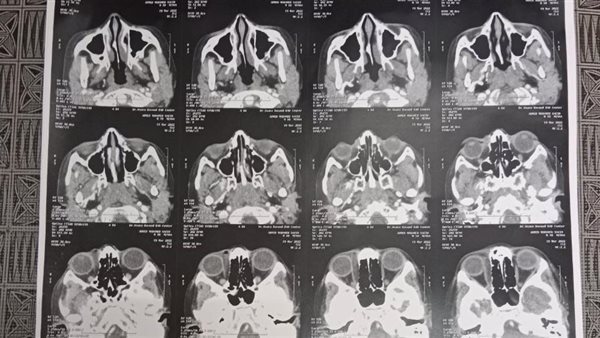

كشف وكيل وزارة الصحة في محافظة الشرقية، الدكتور هشام مسعود، عن إجراء عملية جراحية لاستخراج جسم غريب مهمل داخل تجويف العين، عبارة عن نصف قلم جاف، حيث تم إجراء العملية لطفل عمره ١٢ عاما، وذلك في مستشفى الرمد.

وأوضح وكيل وزارة الصحة في محافظة الشرقية، أن أسرة الطفل توقعوا أنها كدمة منذ أكثر من شهرين، مشيرا إلي أنه لم يظهر جلياً من خلال الأشعة المقطعية، حيث قام الفريق الطبي بإجراء العملية الجراحية بنجاح واستخراج القلم، وسط حالة من الذهول من أسرة الطفل.